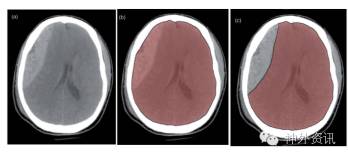

该研究纳入22例患者,平均年龄59.15岁。其中,5例急性硬膜外血肿(epidural hematoma,EDH),17例亚急性或慢性硬膜下血肿(subdural hematoma,SDH)。采集患者年龄、性别、血肿类型和部位等临床资料以及术前、术后和术后1-2月随访的脑CT图像。将CT图像资料输入OsiriX软件,应用分割图像协定法计算全脑HU值(图1、2)。通过重复测量方差分析,结果显示术前与术后(p=0.03)、随访期(p<0.1)的CT图像HU值有显著差异;而CT密度与患者年龄、性别、血肿部位及血肿类型等没有明显相关性。

图1. 将图像分割协定法应用于硬膜外血肿患者的实例:a.右侧硬膜外血肿;b.全脑结构的图像分割;c.从图像中手工去除血肿。